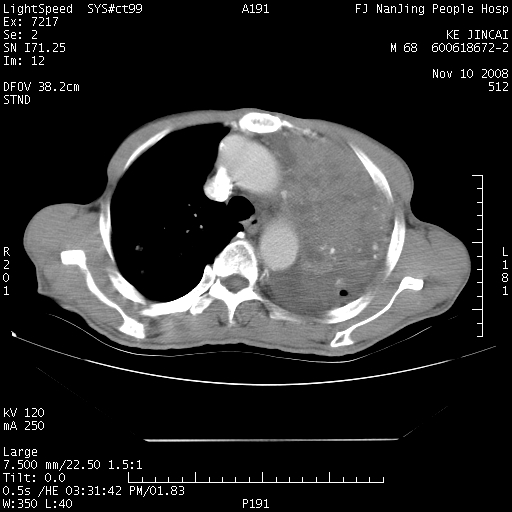

是个很有看头的病例,咋人气那么不旺?没多少人兴趣呢?这个病例几大怪:1   恶性肿瘤侵犯心肌左房怪,心肌一般不会被恶性肿瘤侵犯吧?2   左下肺均匀实变怪,内无含气,有别一般不张实变,含气肺泡完全为液体取代,而非一般不张实变的肺萎陷,冷不丁还以为是肿大的脾脏3   肿瘤本身怪,像tb肺不张4   这么有看头的病例没人气怪。呵呵。

追查病史,咳嗽,患者无发热,血象不高。据说2年前胸片检查怀疑肺ca曾行纤支镜检查,病理未见到癌细胞。无确切资料。

左肺恶性肿瘤侵犯肺动脉,左心房内瘤栓,胸膜转移。